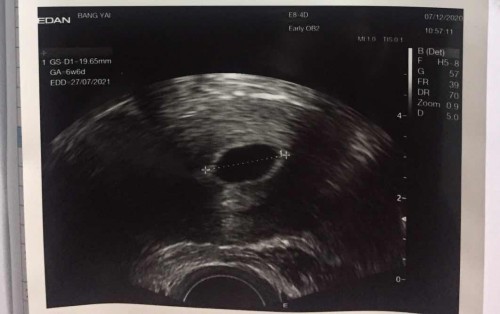

แบบนี้ท้องลมหรือเปล่า

รอดูว่าจะมีตัวอ่อนหรือป่าว

ยังอ่อนอยู่ค่ะ ในจอขึ้น 6วีค6วัน มีโอกาสเจอได้จนถึง 12 วีค เกินนี้คอนเฟิร์มเลยว่าท้องลม

อัพเดตนะคะ ล่าสุดไปหาหมอมาแล้วได้ยินเสียงหัวใจน้องแล้วนะคะ🥰🥰🥰🥰